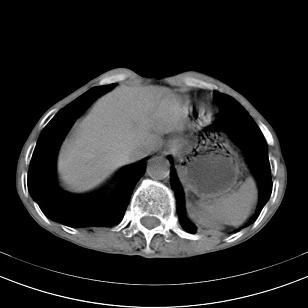

标题: 男,65岁,反复右上腹痛, [打印本页]

标题: 男,65岁,反复右上腹痛,

胃镜提示十二指肠占位